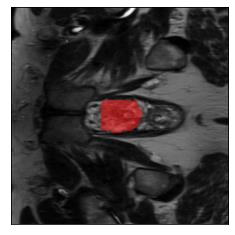

Machine learning models are typically deployed in a test setting that differs from the training setting, potentially leading to decreased model performance because of domain shift. If we could estimate the performance that a pre-trained model would achieve on data from a specific deployment setting, for example a certain clinic, we could judge whether the model could safely be deployed or if its performance degrades unacceptably on the specific data. Existing approaches estimate this based on the confidence of predictions made on unlabeled test data from the deployment's domain. We find existing methods struggle with data that present class imbalance, because the methods used to calibrate confidence do not account for bias induced by class imbalance, consequently failing to estimate class-wise accuracy. Here, we introduce class-wise calibration within the framework of performance estimation for imbalanced datasets. Specifically, we derive class-specific modifications of state-of-the-art confidence-based model evaluation methods including temperature scaling (TS), difference of confidences (DoC), and average thresholded confidence (ATC). We also extend the methods to estimate Dice similarity coefficient (DSC) in image segmentation. We conduct experiments on four tasks and find the proposed modifications consistently improve the estimation accuracy for imbalanced datasets. Our methods improve accuracy estimation by 18\% in classification under natural domain shifts, and double the estimation accuracy on segmentation tasks, when compared with prior methods.